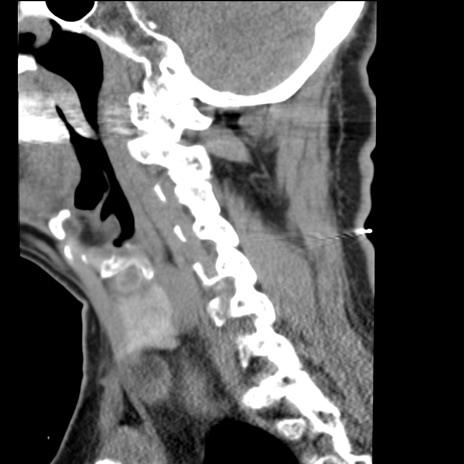

症例50 頚椎CT(矢状断像)

頚椎CT